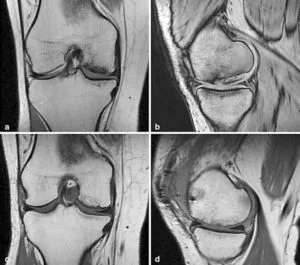

Autologous Chondrocyte Implantation (ACI) is an advanced procedure that uses a patient’s own cartilage cells to repair joint damage, especially in the knee. It is highly effective for individuals dealing with:

Autologous Chondrocyte Implantation (ACI) is a regenerative treatment that uses a patient’s cartilage cells to repair joint damage, restoring function and relieving pain effectively.

The full name of ACI is Autologous Chondrocyte Implantation, an advanced procedure that repairs damaged cartilage using a patient’s own cells, promoting joint healing and improved mobility.

ACI surgery recovery typically takes 6 to 12 months, including initial healing, gradual weight-bearing, and rehabilitation therapy to restore joint function and mobility effectively.